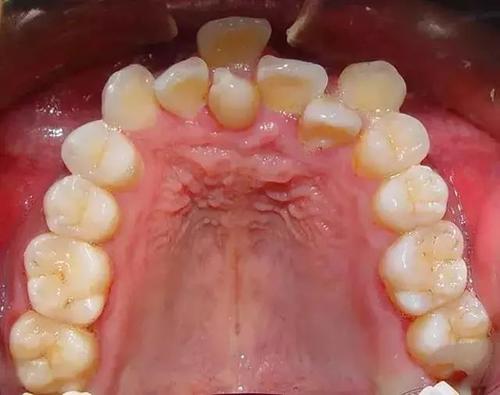

三、广州壹加壹口腔正畸技术好不好?见证苏文新博士和齐志峰博士的隐形牙齿矫正案例:1 .广州壹加壹口腔医院苏文新医生做的隐形牙矫治案例: